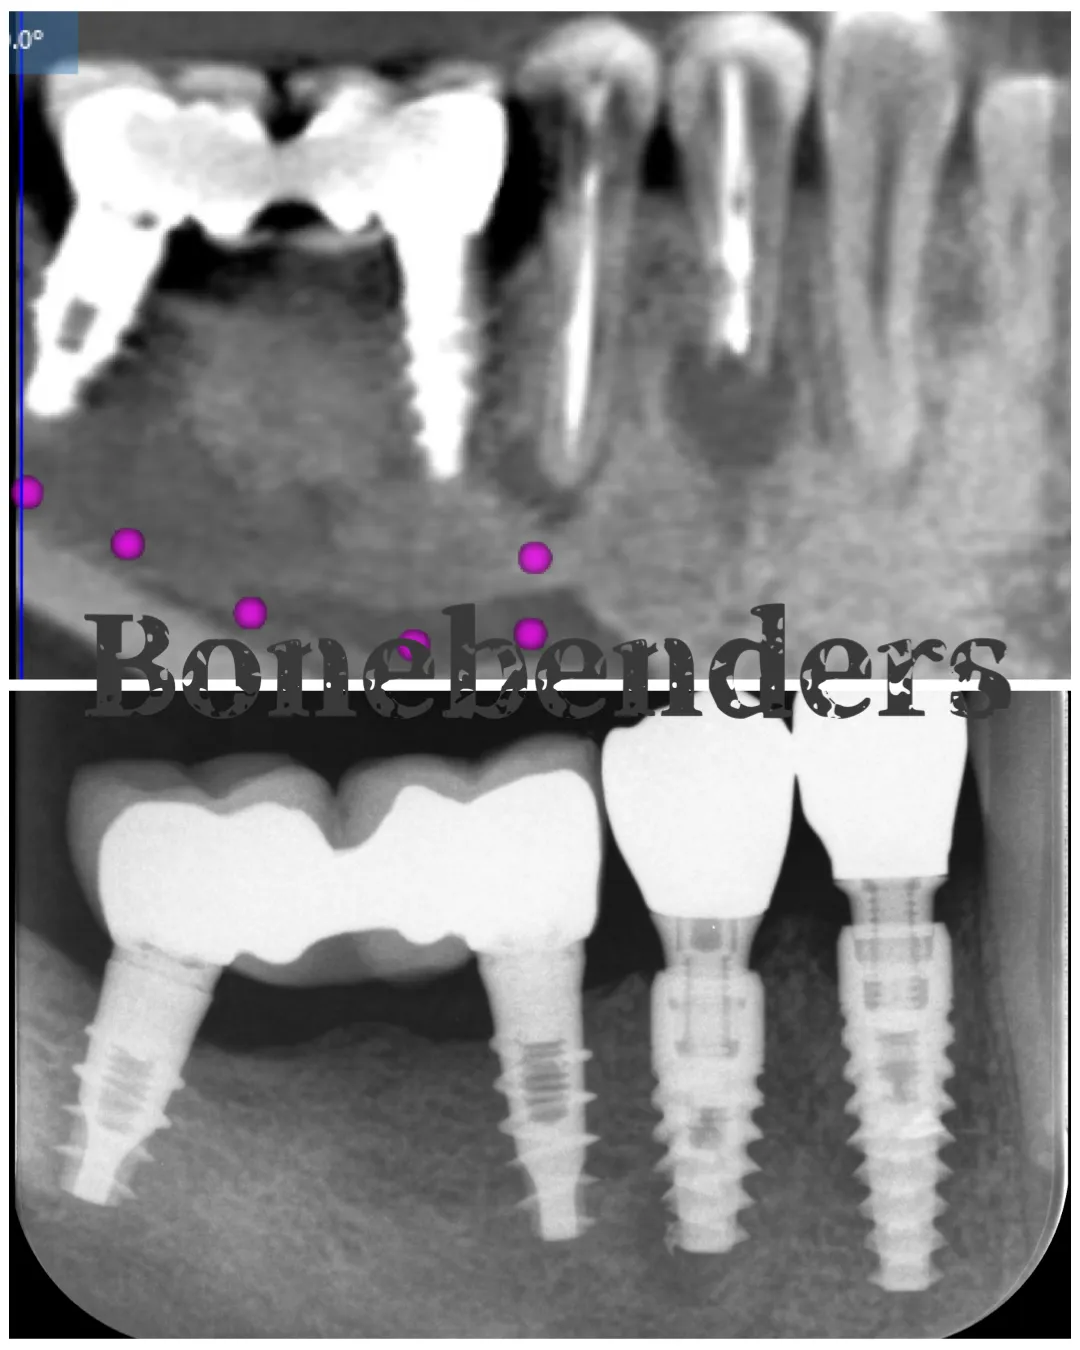

Espansione ERE e impianto immediato: un premolare in una seduta

Caso clinico: espansione crestale ERE con impianto immediato e rigenerazione simultanea. Da ponte fallito a impianto in un'unica seduta.

Caso clinico LMSF graftless: due impianti a 1.6/1.5 con espansori a vite calibrati. Gestione localizzata del seno mascellare, senza innesto.

L'espansione crestale ERE di Bruschi-Scipioni: cos'è, quando si fa, cosa dicono le evidenze. Il pilastro del bonebending in implantologia.

Caso clinico di carico immediato su rialzo crestale del seno mascellare con espansori. Espansione apicale, stabilità >50 Ncm, provvisorio immediato e co...

La tecnica split crest espande le creste sottili per consentire il posizionamento implantare. Indicazioni, strumentazione e risultati clinici.

Espansione crestale - ERE: 98% di successo. Perché molti dicono il contrario e la denigrano? Conflitti d'interesse e dati scientifici reali.